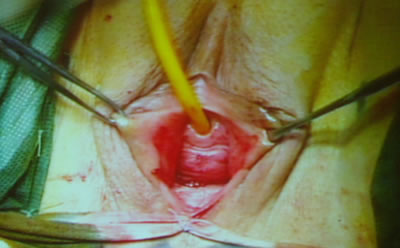

Далее Олег Борисович провел специальным проводником синтетическую

полипропиленовую петлю через отмеченные на коже места. Петля

прошла снаружи внутрь через запирательное отверстие. Пальцем,

введенным в разрез у уретры оператор контролировал прохождение

кончика проводника. Когда инструмент оказался в ране, профессор

провел с помощью его конец петли. Тоже он проделал с другой

стороны. Оператор отрегулировал минимальное натяжение петли,

срезал избытки ее концов. Раны ушил.